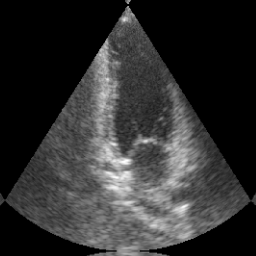

Transthoracic echo is one of the most common means of cardiac studies in the clinical routines. During the echo exam, the sonographer captures a set of standard cross sections (echo views) of the heart. Each 2D echo view cuts through the 3D cardiac geometry via a unique plane. Consequently, different views share some limited information. In this work, we investigate the feasibility of generating a 2D echo view using another view based on adversarial generative models. The objective optimized to train the view-conversion model is based on the ideas introduced by LSGAN, PatchGAN and Conditional GAN (cGAN). The size and length of the left ventricle in the generated target echo view is compared against that of the target ground-truth to assess the validity of the echo view conversion. Results show that there is a correlation of 0.50 between the LV areas and 0.49 between the LV lengths of the generated target frames and the real target frames.